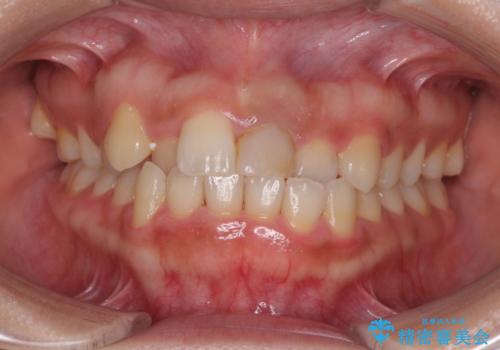

前歯のデコボコを治したい インビザラインによる矯正治療

受け口 マウスピースで矯正治療 難易度:中

上の前歯が一部引っ込んでいる 下のがたがた マウスピース矯正

インビザラインによる受け口の治療 機能性反対咬合の経過